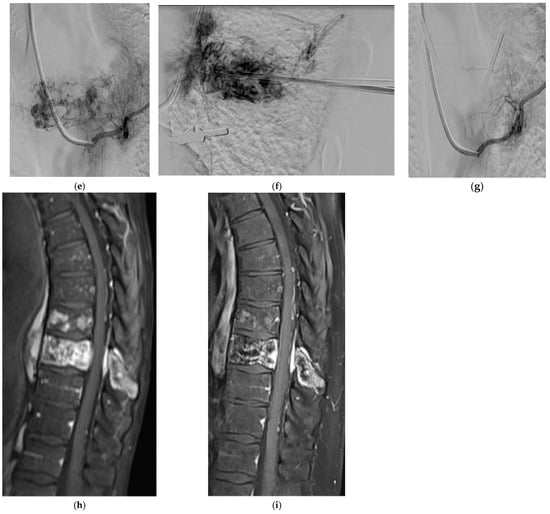

2.6. Fibro-Osseous

Fibrous Dysplasia